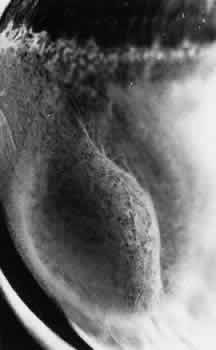

DEGENERATIVE RETINOSCHISIS

Degenerative retinoschisis, a more extensive trophic process, presents as a round or ovoid area of retinal splitting with a smooth fusiform elevation of the inner layer (Fig. 17). The schisis is surrounded on all sides by typical cystoid degeneration; the retinal pillars of the cystoid degeneration as well as the broken pillars near the margin of the schists are prominent. Vessels are located in the inner retinal layer, the intraretinal cavity is optically empty, and the outer retinal layer is moderately irregular in contour.13,14

Fig. 17. Typical degenerative retinoschisis.Note extensive region of typical cystoid degeneration with a rounded and elevated posterior margin. In the center (arrow), radial columns are randomly disrupted, causing a disturbance in coarse surface pattern. (× 18.)

In one type of degenerative retinoschisis, the thin inner wall is composed of the internal limiting membrane, the nerve fiber layer, and retinal vessels (Fig. 18). The irregular outer wall contains portions of the inner nuclear, outer plexiform, outer nuclear, external limiting, and rod and cone layers. At the margin of the cavity, the retinoschisis blends with typical cystoid degeneration and may be relatively flat. Lesions with this appearance have been termed typical degenerative retinoschisis.

Typical degenerative retinoschisis is present in 1% of adult patients and is bilateral in 33% of these patients; therefore, it is evident in 0.7% of adult eyes (see Table 3), with a predilection for location in the inferior temporal quadrant. A narrow band of typical cystoid degeneration is always present between the ora serrata and the anterior border of the schisis cavity; the involved area may extend to or somewhat posterior to the equator.

On clinical examination, typical degenerative retinoschisis appears as round or ovoid areas of retinal splitting with fusiform elevation of the inner layer (Fig. 19). The stippled pattern of surrounding typical cystoid degeneration extends on the inner layer for a variable distance; centrally the inner layer, which contains the blood vessels, is thin and smooth. On contact lens ophthalmoscopy, the inner layer is finely textured, some of the retinal vessels are attenuated, and there is a variable number of tiny, glistening, white dot opacities on the vitreous side. The outer layer, found external to the optically empty cavity, is best seen with indirect ophthalmoscopy when it becomes white on scleral depression. It is somewhat uneven, giving an appearance of finely hammered or beaten metal. Typical degenerative retinoschisis does not extend posteriorly to threaten the macula, and it is not often associated with breaks in either retinal layer; it rarely requires treatment.